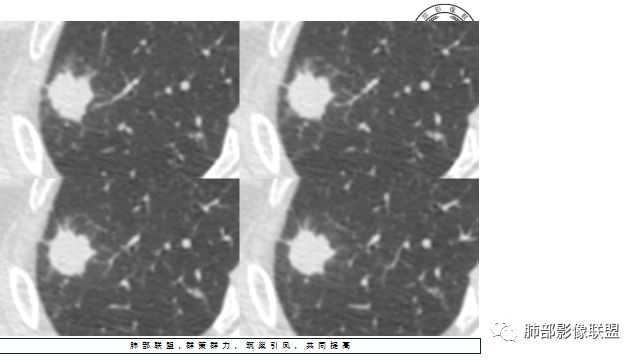

2.右肺尖类圆形结节影,边界清楚,未见明显分叶或深切迹,部分分边缘较平直,可见细长毛刺棘状突起,相邻胸膜增厚,未见胸膜凹陷。后段胸膜下见条索影及微小结节影。

3.平扫病灶密度密度不甚均匀,外侧份见微小高密度影。

4.增强扫描成明显环形强化,中央液化坏死,内壁清楚且较为规整。

2.病灶周边可见薄晕,会想到隐球菌感染,可以出现空洞,但内壁如此清楚的空洞少见。